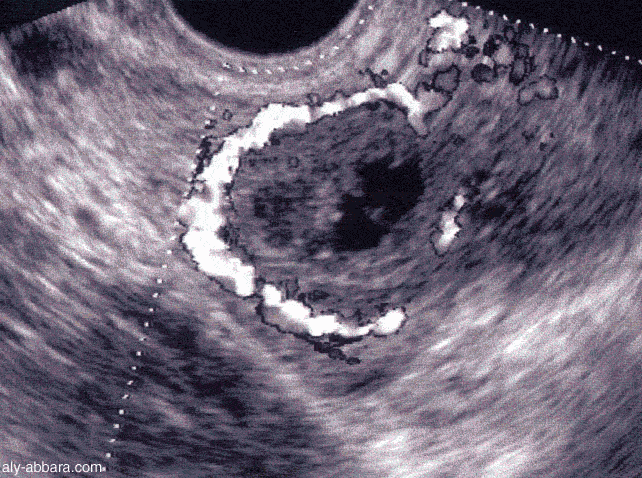

Corps jaune

Le corps jaune est une formation temporaire, au sein de l'ovaire, qui résulte de la transformation du follicule de De Graaf après expulsion de l'ovocyte lors de l'ovulation.

Le corps jaune (corpus luteum) est une formation temporaire, au sein de l'ovaire, qui résulte de la transformation du follicule de De Graaf après expulsion de l'ovocyte lors de l'ovulation.

Ce corps jaune, qui se forme par conséquent dans la seconde partie du cycle de l'ovaire nommée phase lutéale, a pour fonction de sécréter de la progestérone sous contrôle d'une hormone hypophysaire, la LH. La progestérone a pour rôle de maintenir la muqueuse utérine conçue pour accueillir l'embryon lors de la nidation. En cas de non fécondation de l'ovule, le corps jaune dégénère, se flétrit, entraînant avec lui une diminution de la sécrétion de la progestérone et finalement la naissance des règles correspondant au début d'un nouveau cycle. Si l'embryon se fixe, le corps jaune va se maintenir et produire de la progestérone au cours du début de la grossesse. Il disparaît vers le 4e mois quand le placenta prend une autonomie suffisante. Quand cette production cessera brutalement, la muqueuse utérine se décrochera et ce sera l'accouchement.